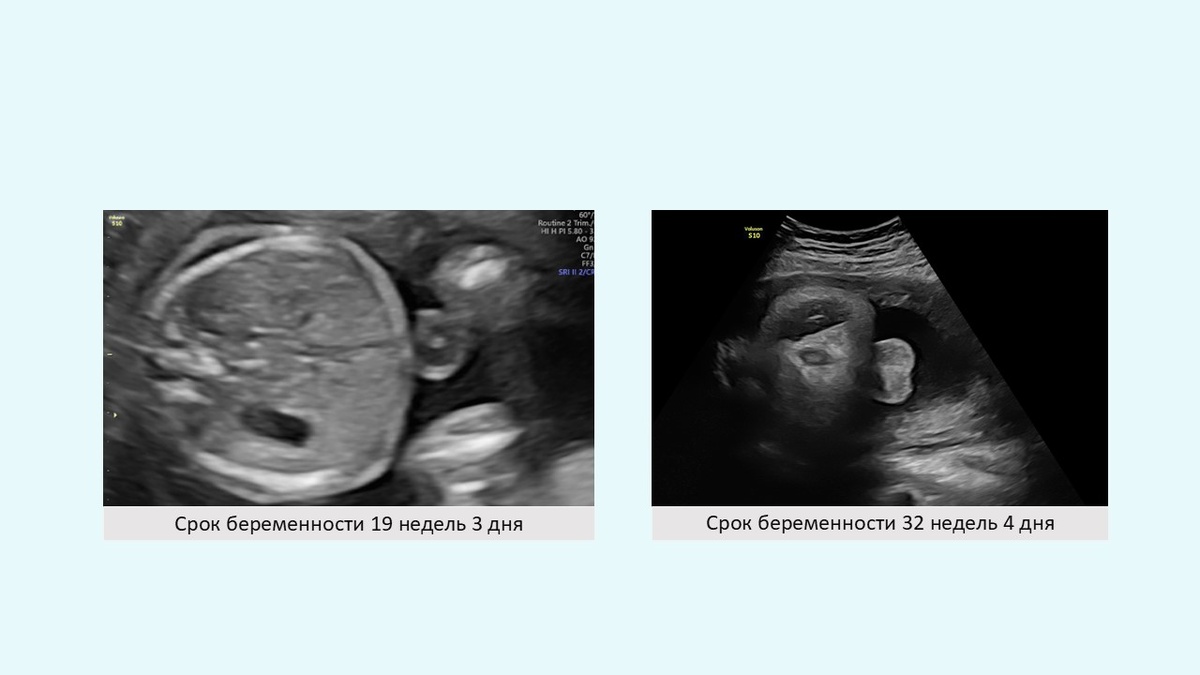

Нормальный, аномальный и отсутствующий "признак мишени" с соответствующим постнатальным изображением.

(A) Изображение нормального целевого признака.                                                                             (B) Изображение аномального по форме и смещенного кпереди признака мишени, а также соответствующее постнатальное изображение отсутствующего ануса в ожидаемом положении, но с фистулой, которая заканчивается в преддверии (прямокишечно-преддвериевый свищ, синяя стрелка).

(C) Изображение отсутствующего целевого признака вместе с соответствующим постнатальным изображением порока развития клоаки, при котором мочевыводящие пути, влагалище и прямая кишка имеют один общий канал (синяя стрелка).

Нормальный, аномальный и отсутствующий "признак мишени" с соответствующим постнатальным изображением. (A) Изображение нормального целевого признака. (B) Изображение аномального по форме и смещенного кпереди признака мишени, а также соответствующее постнатальное изображение отсутствующего ануса в ожидаемом положении, но с фистулой, которая заканчивается в преддверии (прямокишечно-преддвериевый свищ, синяя стрелка). (C) Изображение отсутствующего целевого признака вместе с соответствующим постнатальным изображением порока развития клоаки, при котором мочевыводящие пути, влагалище и прямая кишка имеют один общий канал (синяя стрелка).